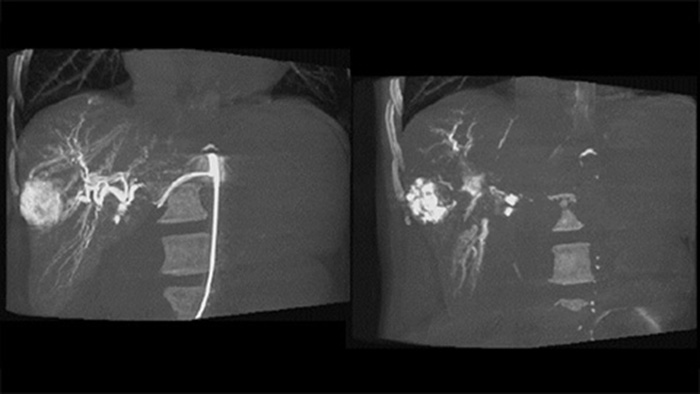

Imágenes 3D posteriores a la embolización con la THC

Una adquisición 3D posterior a la embolización le permite ver el depósito dirigido del material embólico, como Liopidol o perlas radiopacas, en el tumor.5.

Fusión de imágenes 3D antes y después de la embolización con Dual View

Dual View permite ver de forma simultánea la imagen 3D de la fase arterial antes de la embolización y la imagen después de la embolización para evaluar el fin del tratamiento.